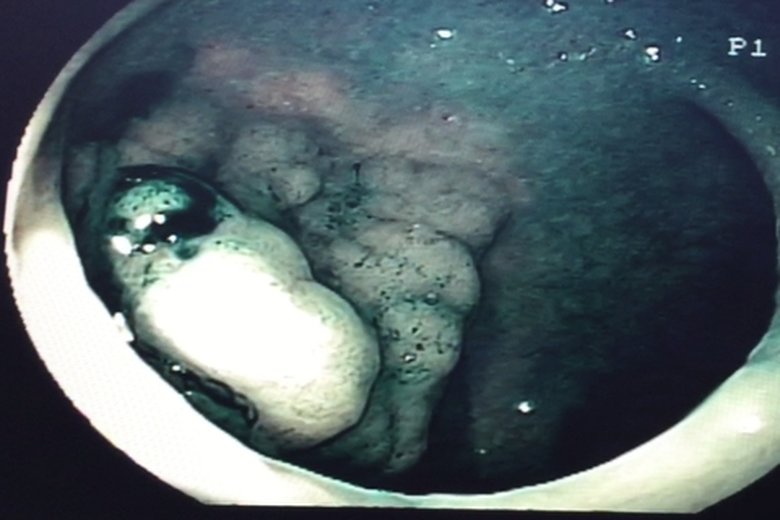

內視鏡切除瘜肉免動刀

醫生操作時將一根導管與攝像儀探入大腸內,以查看大腸內部的狀況。圖為內視鏡光源照射瘜肉組織外觀(衛福部朴子醫院提供)

【新唐人亞太台 2015 年 12 月 11 日訊】家族有患大腸瘜肉,或家族史患有大腸癌或線性瘜肉,是罹患大腸癌的高危險群。大腸瘜肉演變為大腸癌之前症狀不明顯,除非瘜肉已經大於1公分或已到晚期才會出現不適的症狀。大腸內視鏡做檢查,可早期發現大腸性瘜肉並切除,有效降低大腸癌的發生率。

國民健康署2011年最新癌症統計,男女性大腸癌發生率多在40歲以後,大腸癌在55-64歲年齡層為發病高峰,原因是飲食西化,外食比率高、多油、多肉、低纖維的食物。大腸癌在零期或一期的治療研究顯示,存活率可以高達百分之80以上。定期大腸鏡檢查是預防大腸癌的不二法門。

50歲以上成人最好定期至醫院作糞便篩檢及大腸鏡檢查。若有1.血便、肛門出血或黏液變多;2.排便習慣改變、便秘或腹瀉;3. 排便不乾淨或有便意但排不出;4.體重驟減等,應盡速至醫院就診尋求專業醫師診治。